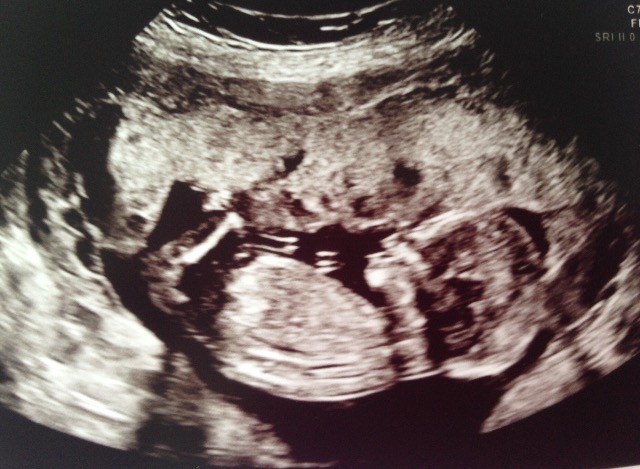

Ja mam bardzo podpbnie i w 9dpt beta 41 [emoji5] badz dobrej mysli Kochana [emoji9] [emoji9] trzymam kciuki! [emoji173]Dziewczyny jestem dzis 7 dpt 3-dniowego zarodka i martwię się, bo wczoraj po południu i dziś od rana pojawia się momentami ból brzucha podobny do tego na @...